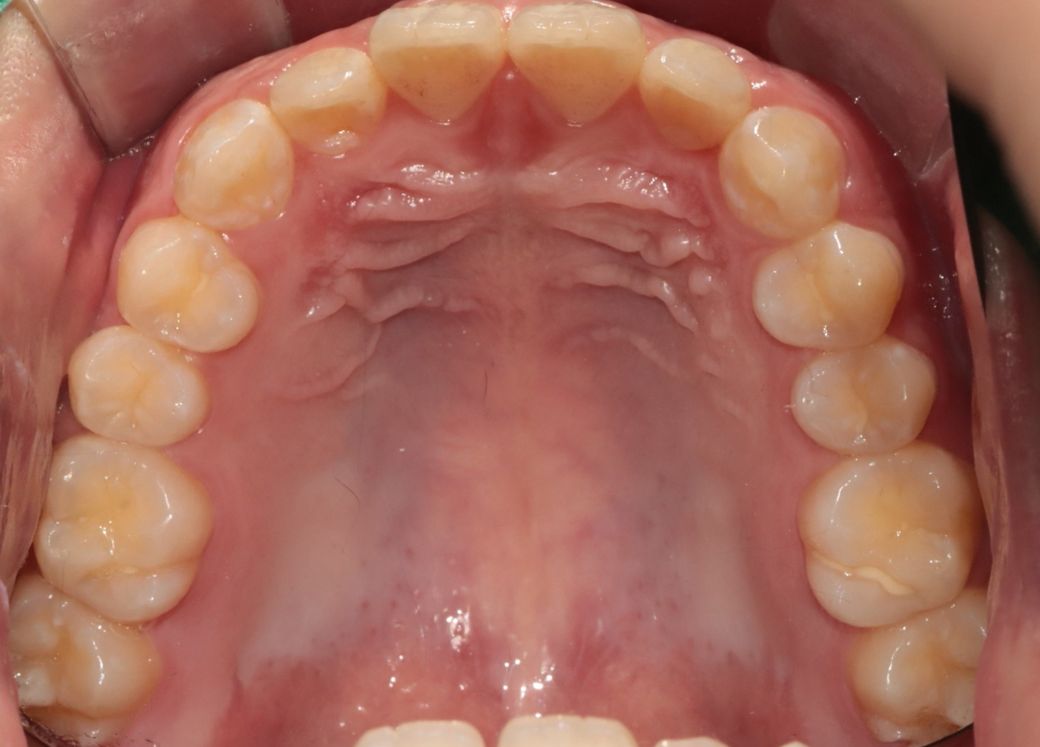

• 3번 째 사진

세가지 치과 모두 맞는 말입니다. 지금 보여주신 자료를 종합해보면 경미한 3급 부정교합입니다.

이 상태에서 교정도 가능하고 양악도 가능하지만 치료 이후 변화되는 모습에는 한계가 있습니다. 또한 부정교합 및 골격부조화가 심하지 않으므로 심미적으로 불편감이 없다면 3번 치과처럼 치료하지 않아도 됩니다. 물론 심미적으로 문제가 된다고 생각한다면 이때는 두가지 방법 모두 가능합니다.